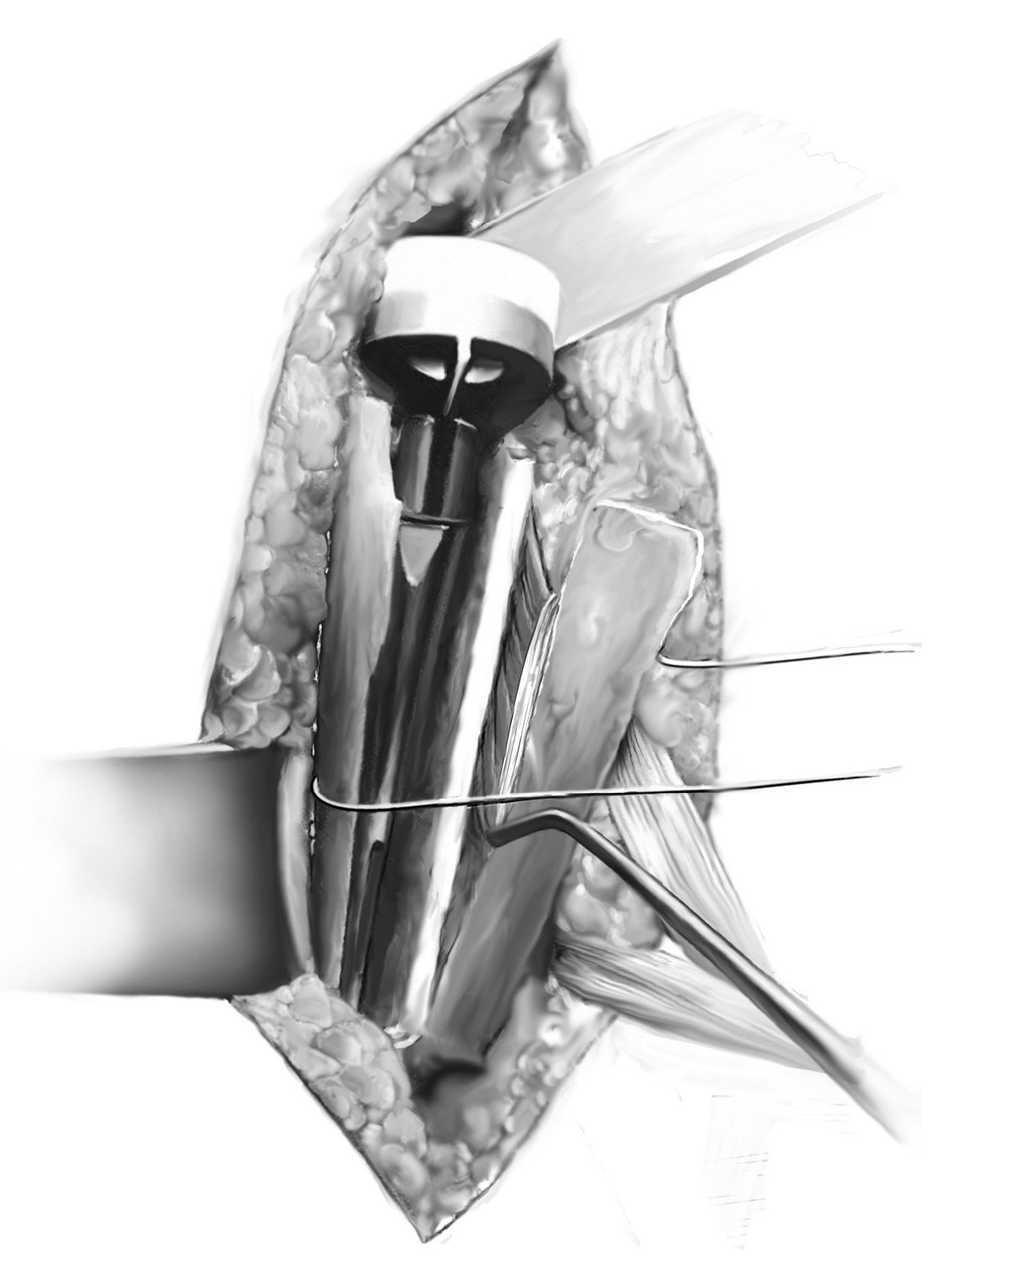

Figuras 9a y 9b. Reducción de la ventana ósea pediculada al pectoral mayor y fijación del húmero proximal mediante cerclaje. Como último test de tensión se coloca de nuevo el componente de prueba. Si queda demasiado laxo, se puede atornillar una extensión humeral (+ 9 mm). Se estabilizan los restos de manguito de los rotadores y de tuberosidades tal y como se habÃa preparado previamente, suturas no reabsorbibles de alta resistencia a la tensión (p. e., Fiber-wire N.º 2 Arthrex Co., Karlsfeld/Múnich, Alemania, Orthocord, Mitek Co., Kirkel-Limbach, Alemania, o Ethibond N. º 3-5, Ethicon Co., Norderstedt, Alemania; a). Los cerclajes de sutura previamente preparados se doblan hacia la prótesis hasta alcanzar la reducción más anatómica posible y la fijación del húmero proximal (b). Si falta rotación externa, se puede considerar la posibilidad de realizar una transferencia muscular de latissimus dorsi o teres major según técnica de L'Episcopo9. Finalmente, se valoran de nuevo el arco de movilidad y la estabilidad del implante. Drenaje de aspiración y cierre de la herida con suturas de adaptación en el surco deltopectoral.